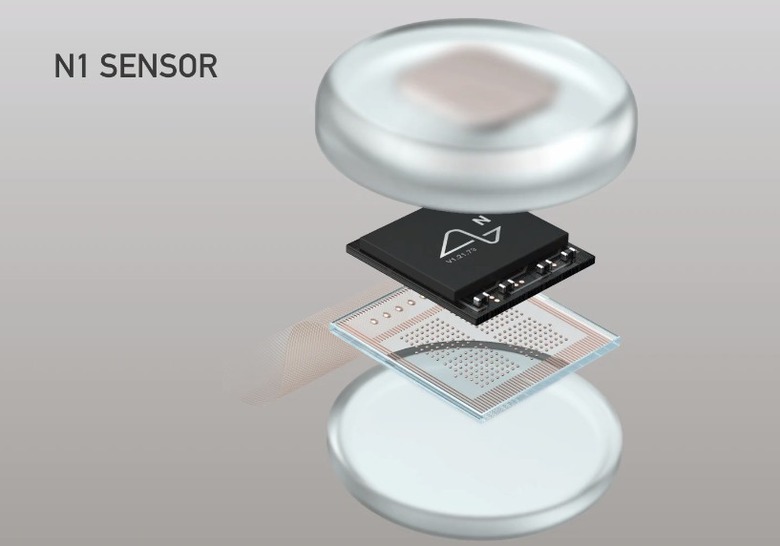

According to the article, its bundles of flexible threads are about one quarter the diameter of a human hair, implanted using needles to avoid blood vessels on the brain's surface. Then the embedded sensors capture information and send it to a receiver (the chip above) on the surface of the skull. From there it transmits wirelessly — Elon Musk said it could Bluetooth the information to your skull. Right now implantation requires drilling holes, but researchers hope in the future they can use lasers to avoid "unpleasant" vibration.

The pod itself is worn behind the ear, with the wireless, battery and other hardware in there.

According to Musk, its current v1 4x4mm chip is capable of 10,000 electrodes with "read and write" capability, which he says is more than 1,000 times the number of the best deep brain interface currently available for Parkinson's treatment.